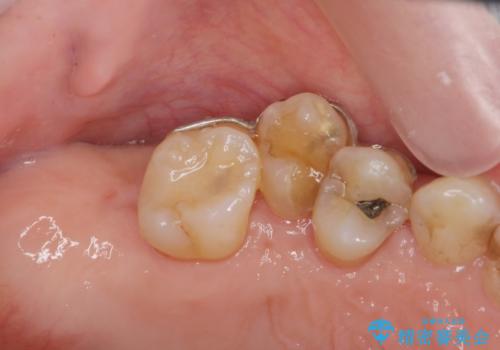

部分矯正を含む 歯周病治療 (再生治療・歯周ポケット除去・MTM・連結補綴)

連結補綴について

特定の歯に強く力がかかりまた歯周病により臨床歯根が短くなっているような場合、歯の動揺を抑えるため連結補綴が検討されます。

歯の動揺が続くとより周囲の骨を失い最終的には歯を喪失してしまう可能性が高くなってしまうためです。

今回連結補綴を行うにあたり、歯周病の問題を解決するために再生療法・歯周ポケット除去手術を、またより歯の神経を保存し力に対抗できる環境を整えるために小矯正を行い精度の高いメタルボンドクラウンを製作することができました。